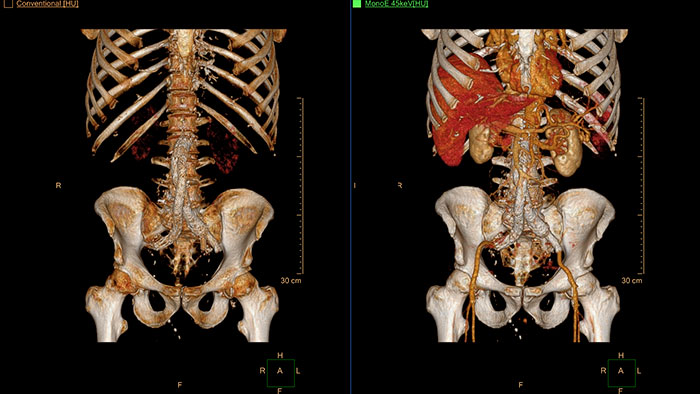

IQon Spectral CT is the only scanner to offer CT Spectral Light Magic Glass and CT Spectral Magic Glass on PACS, helping radiologists review and analyze multiple layers of spectral data at once, including on their PACS.

The spectral viewer is optimized for analysis of spectral data sets from the IQon Spectral CT Scanner. Obtain a comprehensive overview of each patient quickly and easily, quantify quickly, and assist in diagnosis. It is designed to accommodate general spectral viewing needs with additional tools to assist in CT images analysis.